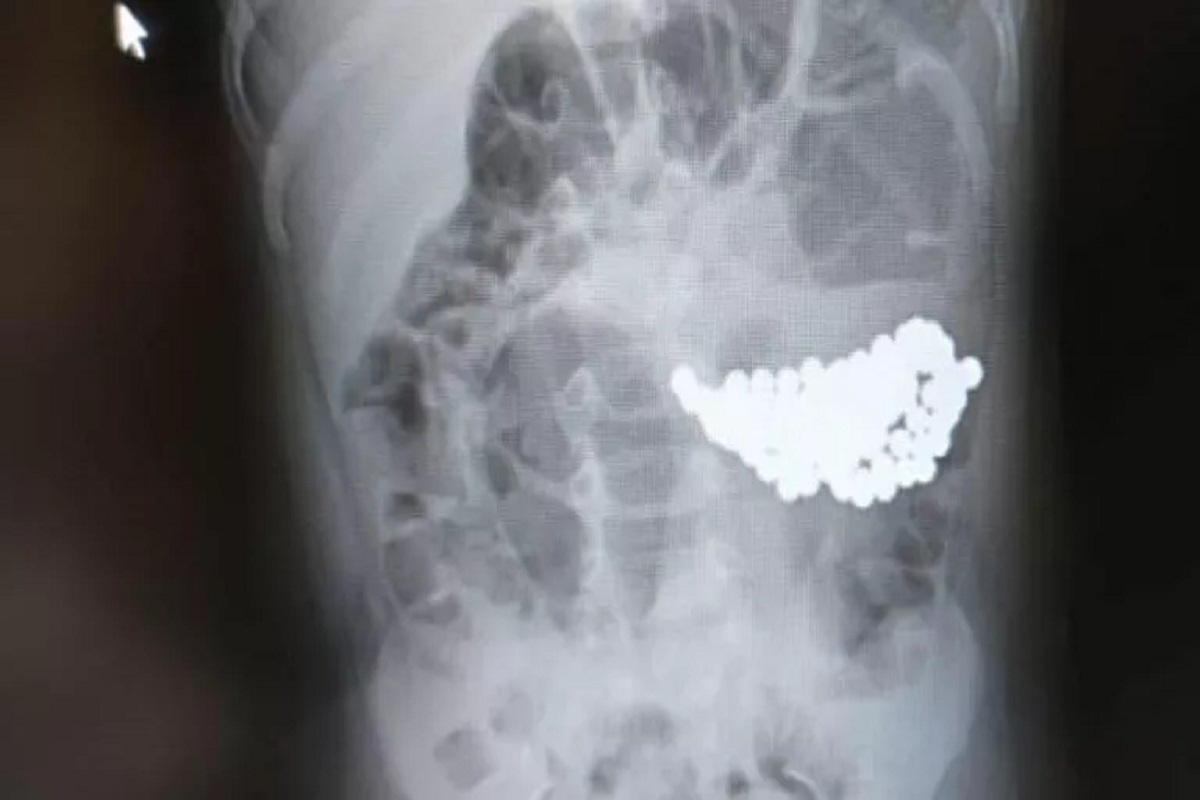

В Волгограде врачи спасли девочку, которая проглотила 134 магнитных шарика.

После обследования выяснилось, что причиной недомогания стала кишечная непроходимость, вызванная большим скоплением инородного тела. Магнитные шарики вызвали конгломерат, который сдавливал стенки кишечника.